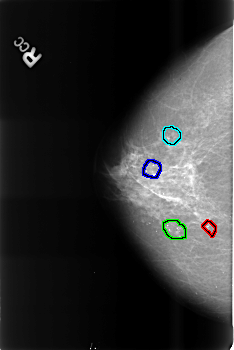

B_3472_1.RIGHT_CC

FILE: B_3472_1.RIGHT_CC.OVERLAY

TOTAL_ABNORMALITIES 4

ABNORMALITY 1

LESION_TYPE CALCIFICATION TYPE PLEOMORPHIC DISTRIBUTION CLUSTERED

ASSESSMENT 2

SUBTLETY 4

PATHOLOGY BENIGN_WITHOUT_CALLBACK

TOTAL_OUTLINES 1

ABNORMALITY 2

ABNORMALITY 3

ABNORMALITY 4